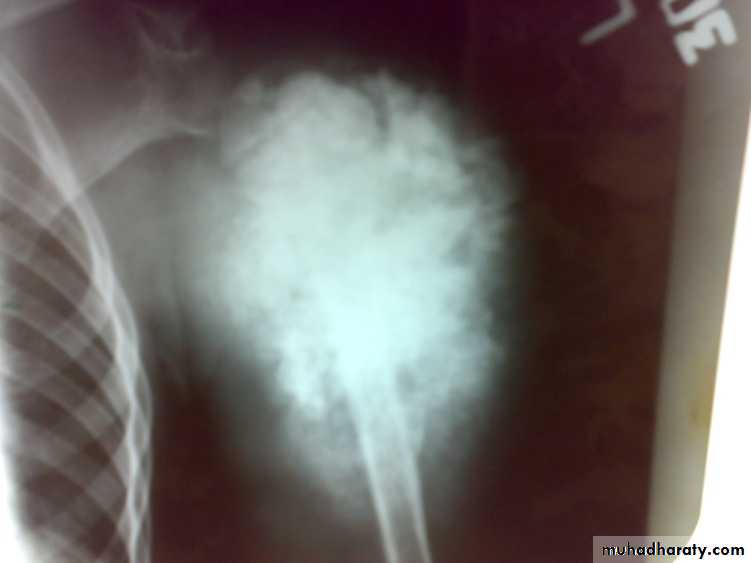

Age : 10-20 years commonly but it may occur in old following irradiation and Paget’s disease.Site: metaphysis of long bone specially around knee and proximal humerus is common sites.

: X-ray are very variable but it show combination of bone destruction and bone formation.

The metaphysis show osteolytic and osteoblastic areas, the cortex is usually perforated and soft tissue shadow may be seen.

There is new bone formation in form of Codman's triangle at periphery of when cortex penetration cause periostium elevation and vertical streaks of calcification in the adjacent soft tissues called sunray appearance.